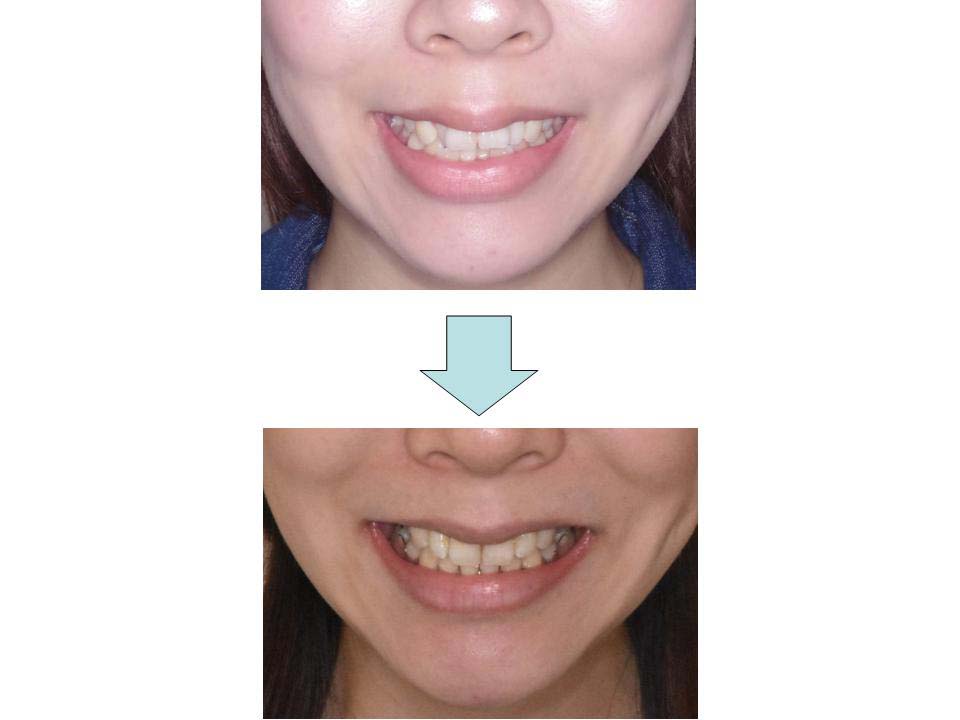

八重歯、上の前歯が出ている

上下前歯の凸凹が大きく、歯とあごの大きさのバランスの乱れを認めたため、上下の歯の抜歯を行って前歯の凸凹を改善しました。患者さんの装置装着状況も良好で上下の歯をきちんとかみ合わせることができました。

| 主訴 | 八重歯、上の前歯が出ている |

| 年齢・性別 | 30歳 / 女性 |

| 抜歯部位 | 上下顎両側第一小臼歯 |

| 装置 | マウスピース型矯正装置(インビザライン) |

| 期間 | 2年10か月 |